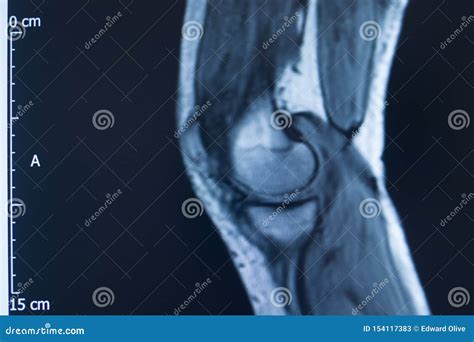

An Mcl Tear Mri is a non-invasive imaging technique that provides detailed images of the knee joint. MRI uses magnetic fields and radio waves to create cross-sectional images of the body’s internal structures. This allows healthcare professionals to visualize the MCL and other soft tissues in the knee, identifying any tears or damage.

During an *Mcl Tear Mri*, the patient lies on a table that slides into a large, cylindrical machine. The procedure is painless and typically takes about 30-60 minutes. The MRI machine captures multiple images from different angles, providing a comprehensive view of the knee joint.

An *Mcl Tear Mri* is particularly useful for differentiating between an MCL tear and other knee injuries, such as meniscal tears or anterior cruciate ligament (ACL) injuries. This information is crucial for developing an appropriate treatment plan.